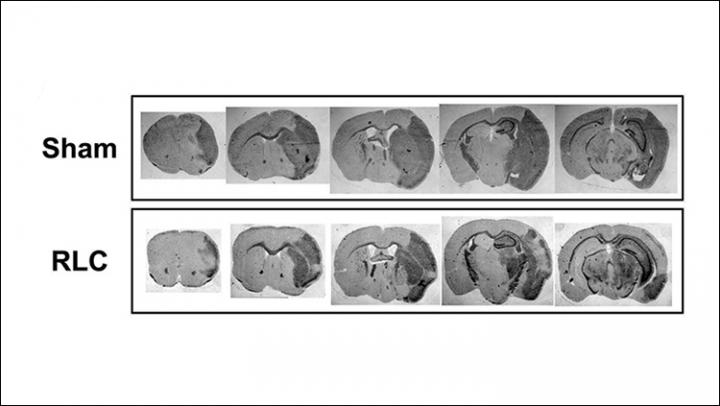

image: Remote ischemic limb conditioning reduces swelling and lesion size (bottom).

Surprisingly, the increase in circulating inflammatory cells was associated with reduced brain tissue damage and swelling and improved motor function. The symptoms improved for both moderate and severe strokes, indicating the potential for wide application as a stroke treatment.